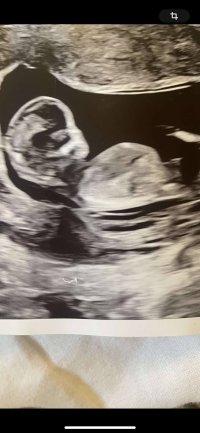

Usikker på om det er nub man ser?13+2 noen som har en tanke her? Synst selv nubben her er mye flatere enn med gutten jeg har

Jeg spurte flere sider, men ene sa at de ikke ville si noe da bare en liten del av Nuben visste så det var vanskelig å si noe om kjønn..Usikker på om det er nub man ser?

Dette er kanskje Nuben?Usikker på om det er nub man ser?

Du hadde rett! Det var navlestrengen. Ingen nub på bildet.Usikker på om det er nub man ser?